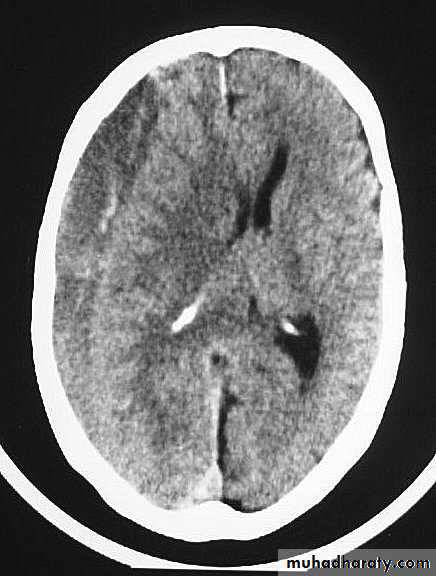

c. Intracerebral Haematoma

This is the least common of traumatic haematoma.

They are due to areas of traumatic contusion coalescing into a contusional haematoma.

Disrupted cerebral tissue release thromboplastins that potentiate haemorrhage.

CT scan: appear as hyperdence lesions with associated mass effect and midline shift.

Large intracerebral haematomas should be evacuated unless the patient’s neurological state is improving.

Small inracerebral haematomas may not require removal, but be aware that they can expand.